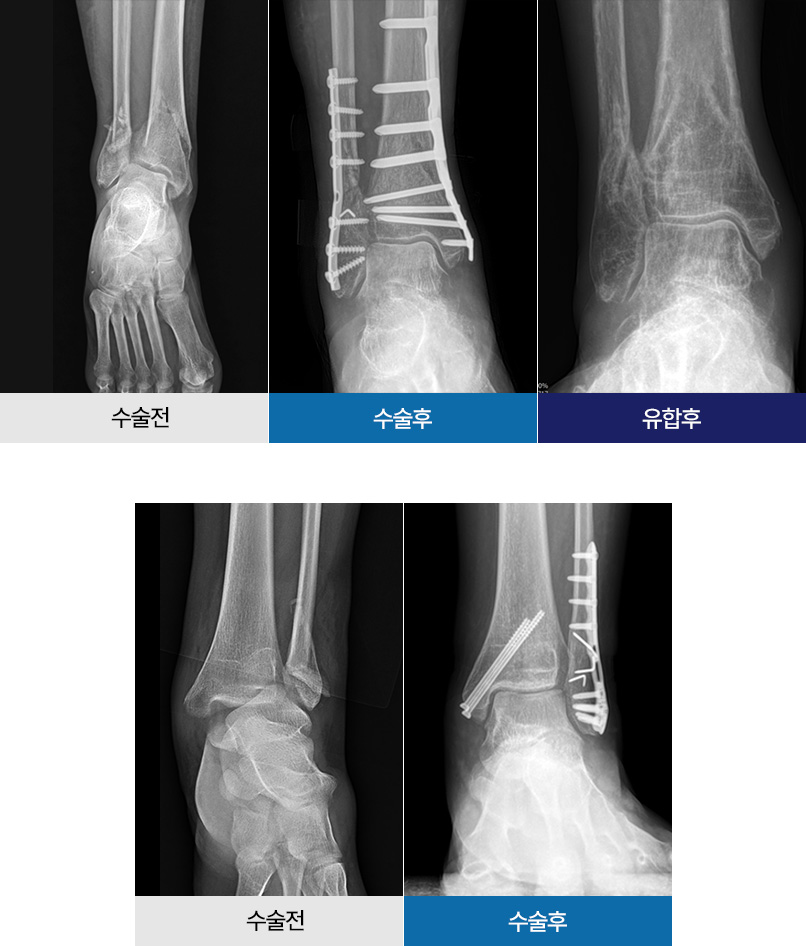

골절된 면을 잘 맞추고 튼튼하게 고정하는 기술력을

서울필병원 족부센터에서 만나보세요.